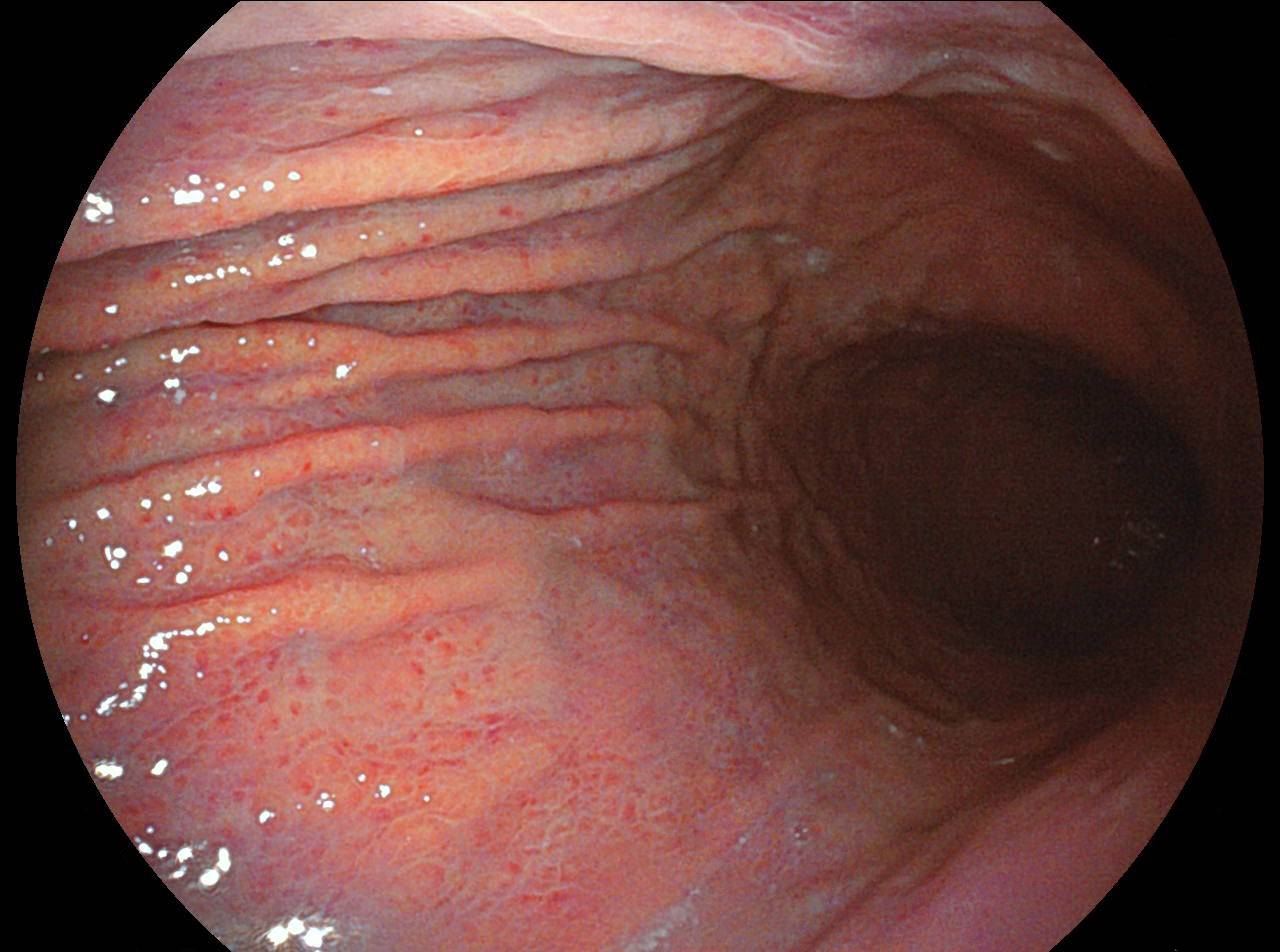

運用高科技尖端影像設備,提供貴賓精準的檢查、判讀、即時醫療、後續追蹤、健康管理或醫學中心轉介服務;從健檢診斷到後端治療,一條龍式服務。永越自成立以來,已服務超過16萬人次,每年通報件數超過千件,揪出包括:甲狀腺癌、肝腫瘤、肺癌、乳癌、子宮頸癌等重大異常的健康警訊,把握住早發現早治療的黃金關鍵。